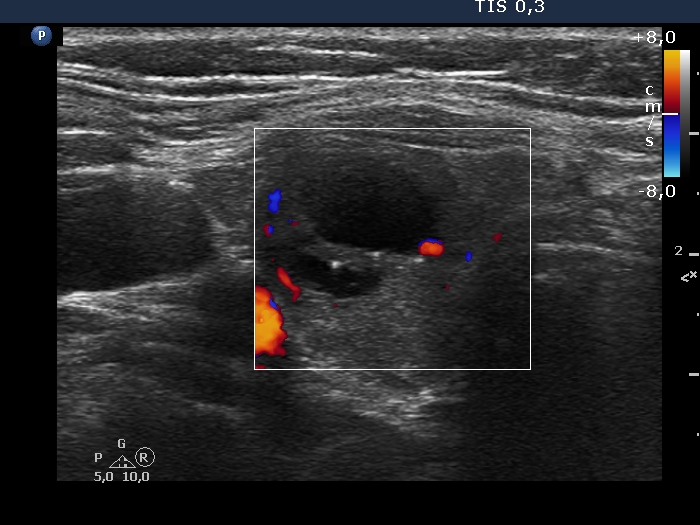

Examination in 2013 (first row of images):

Clinical data. A 50-year-old woman was referred for evaluation of a nodular goiter. The patient has been treated for hypothyroidism for 16 years.

Palpation: Both lobes were a bit firm, no nodule was palpable.

Laboratory test: TSH 4.01 mIU/L on daily 100 microgram levothyroxine.

Ultrasonography. The thyroid was minimally/moderately hypoechoic and had several discrete minimally/moderately hypoechoic lesions.

Cytology was performed from the lesion in the central part of the right lobe and resulted in Hashimoto's thyroiditis.